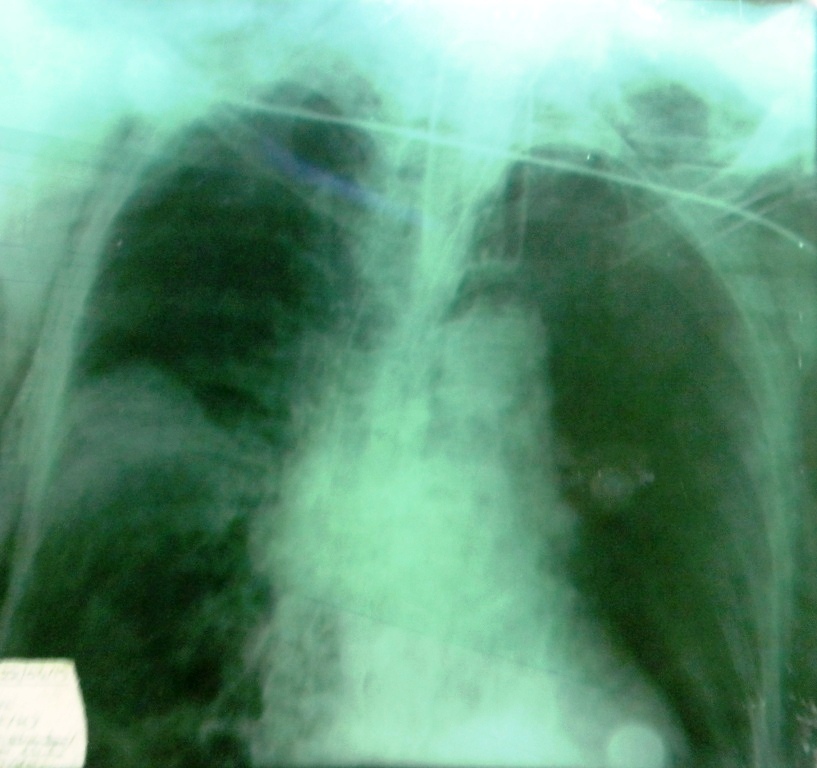

Swine flu is caused by antigenic shift of influenza A virus with clinical features similar to seasonal influenza virus. Majority of the morbidity and mortality due to swine flu are attributable to pneumonia and the acute respiratory distress syndrome (ARDS). Bacterial superinfection can occur, though it is rare in adults. Here we report a case of swine flu superinfected with carbapenem resistant Klebsiella, which is often coined as Klebsiella ‘superbug’.